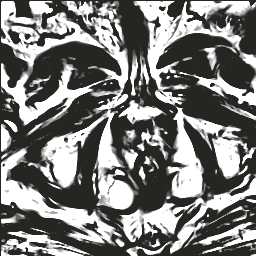

In this paper, we focus on three problems in deep learning based medical image segmentation. Firstly, U-net, as a popular model for medical image segmentation, is difficult to train when convolutional layers increase even though a deeper network usually has a better generalization ability because of more learnable parameters. Secondly, the exponential ReLU (ELU), as an alternative of ReLU, is not much different from ReLU when the network of interest gets deep. Thirdly, the Dice loss, as one of the pervasive loss functions for medical image segmentation, is not effective when the prediction is close to ground truth and will cause oscillation during training. To address the aforementioned three problems, we propose and validate a deeper network that can fit medical image datasets that are usually small in the sample size. Meanwhile, we propose a new loss function to accelerate the learning process and a combination of different activation functions to improve the network performance. Our experimental results suggest that our network is comparable or superior to state-of-the-art methods.